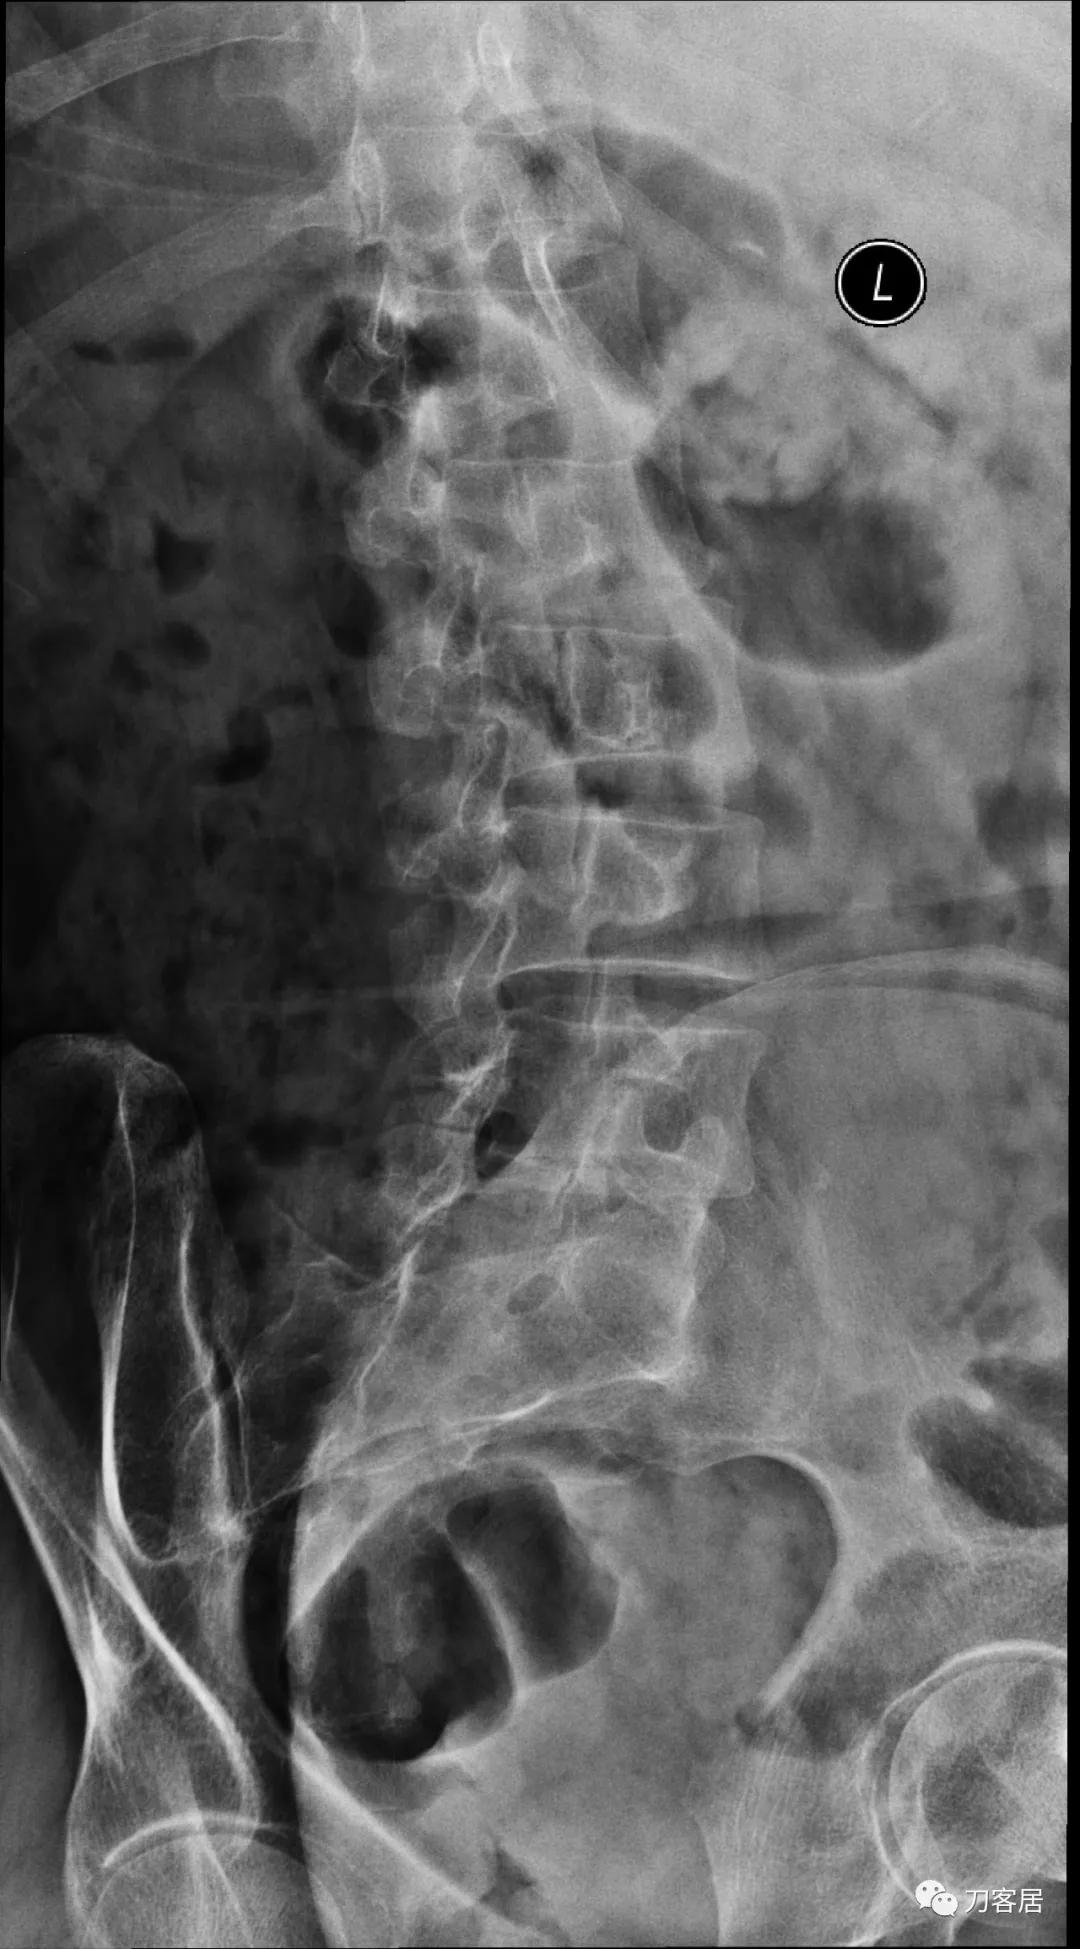

图7. 20210616术前腰椎右斜位X线片

图8. 20210616术前腰椎左斜位X线片